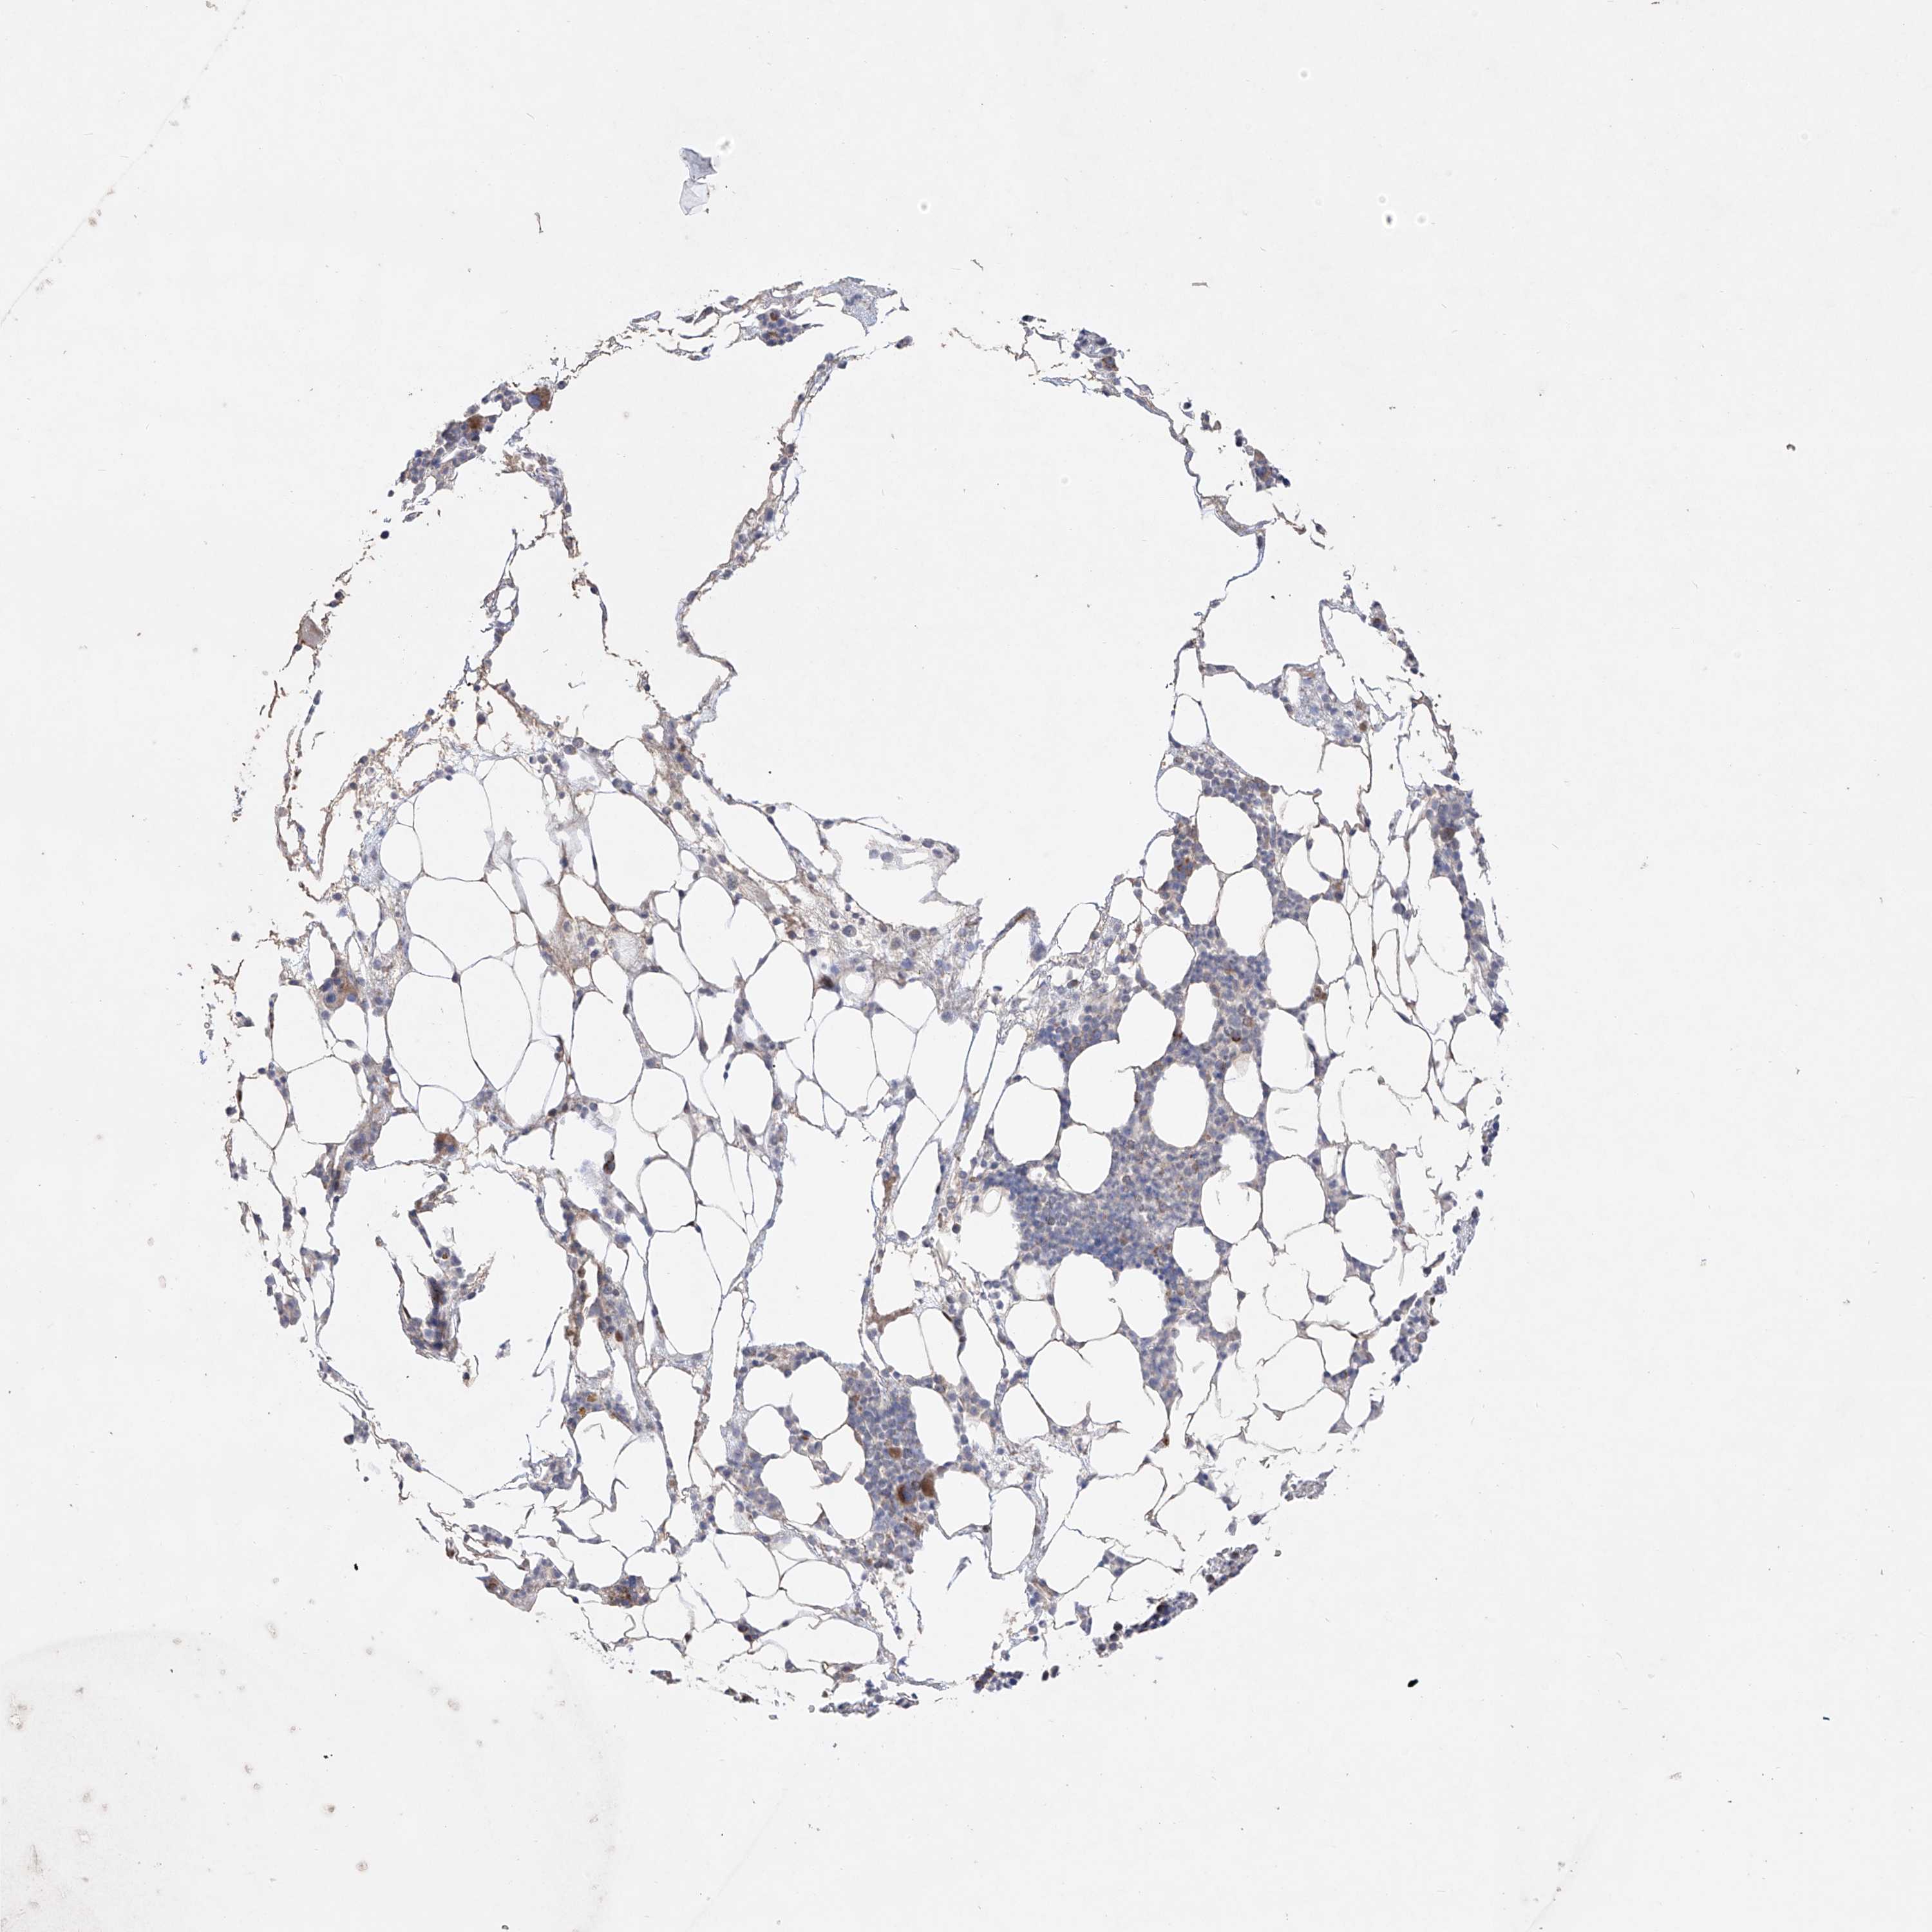

BONE MARROW - Antibody stainingi

Antibody staining in the annotated cell types in the current human tissue is reported as not detected, low, medium, or high, based on conventional immunohistochemistry profiling in selected tissues. This score is based on the combination of the staining intensity and fraction of stained cells.

Each image is clickable and will lead to virtual microscopy that enables deeper exploration of all samples and also displays staining intensity scores, fraction scores and subcellular localization as well as patient and tissue information for each sample.

Antibody HPA030817Antibody HPA030818

Hematopoietic cells MediumLow